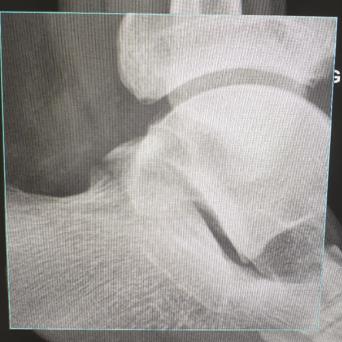

L’image

du jour

Illustration

Cancer de la prostate

Le « Movember » – qui se déroule chaque mois de novembre – a pour but de sensibiliser la population à la lutte contre les cancers masculins, dont le cancer de la prostate qui est en première position (26,5 % des cancers chez les hommes de plus de 65 ans).